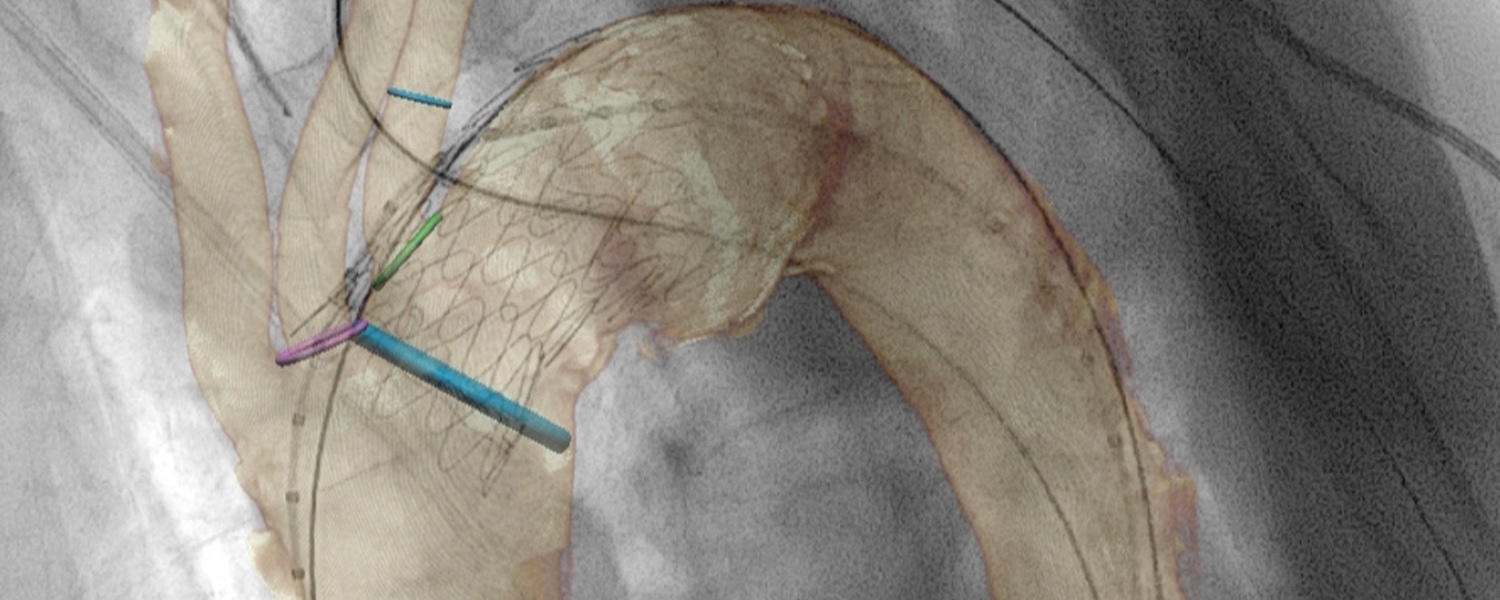

- Thoracic aortic stent grafting